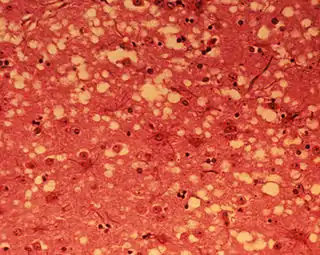

Los síntomas que se observan están motivados por la acumulación del prion en las células neuronales originando la muerte celular. Un análisis microscópico revela lesiones como vacuolas que dan al tejido nervioso un aspecto de esponja.